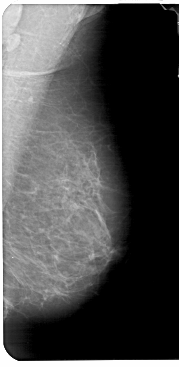

A_1776_1.LEFT_MLO

LEFT_MLO LINES 5491 PIXELS_PER_LINE 2776 BITS_PER_PIXEL 12 RESOLUTION 43.5 OVERLAY